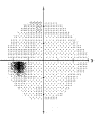

Q

Glaukom

Vilken undersökning är detta och vad visar bilden?

A

Datorperimetri

Synnedsättning typisk för glaukom